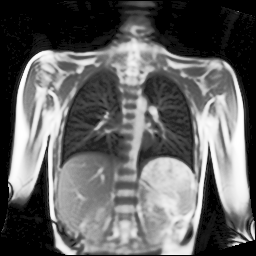

We trained our network on images of a 2D+t magnetic resonance (MR) image series of the lung. Due to the low proton density of the lung parenchyma in comparison to other body tissues as well as strong magnetic susceptibility effects, it is very challenging to acquire MR images with a sufficient signal-to-noise ratio. Recently, a novel MR pulse sequence called ultra-fast steady-state free precession (ufSSFP) was proposed [2]. ufSSFP allows detecting physiological signal changes in lung parenchyma caused by respiratory and cardiac cycles, without the need for intravenous contrast agents or hyperpolarized gas tracers. Multi-slice 2D+t ufSSFP acquisitions are performed in free-breathing.

Refer to captionRefer to captionRefer to captionRefer to captionRefer to captionRefer to captionRefer to captionRefer to captionRefer to captionRefer to captionRefer to captionRefer to captionRefer to captionRefer to caption

Figure 5: Maximum inspiration (top row) and maximum expiration (bottom row) for different slice positions of one patient from back to front.

For a complete chest volume coverage, the lung is scanned at different slice positions as shown in Figure 5. At each slice position, a dynamic 2D+t image series with 140 images is acquired. For the further analysis of the image data, all images of one slice position need to be spatially aligned. We choose the image which is closest to the mean respiratory cycle as fixed image of the series. The other images of the series are then registered to this image. Our data set consists of 48 lung acquisitions of 42 different patients. Each lung scan contains between 7 and 14 slices. We used the data of 34 patients for the training set, 4 for the evaluation set, and 4 for the test set.